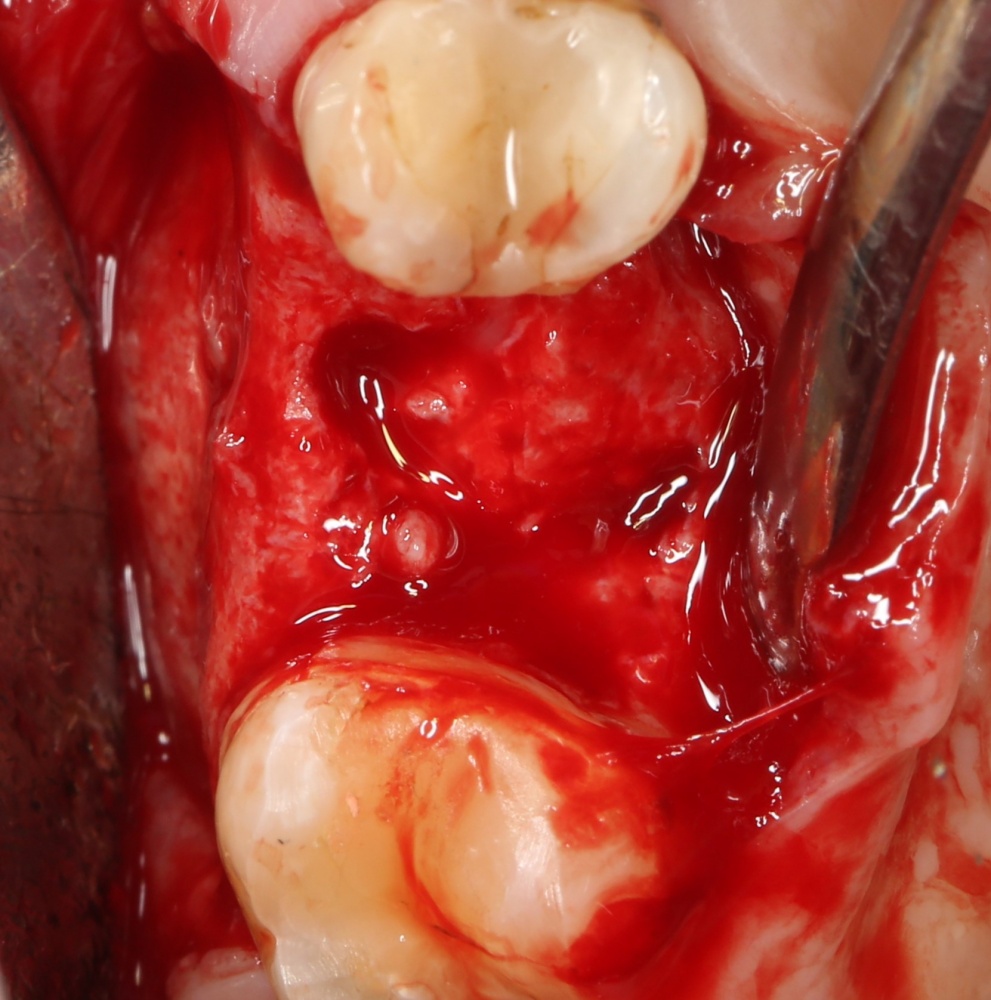

В общем, так и получилось. Уж не помню, почему я наобещал пациентке, что мы поставим ей имплантаты одновременно с остеопластикой. Но я наобещал. И, когда увидел клиническую картину в полости рта:

у меня появились серьезные сомнения, смогу ли я выполнить своё обещание. Вот только не спрашивай меня «Вот чо, сложно было по КЛКТ посмотреть?». Я же не спрашиваю тебя, где ты был в 2013 году, и сделал ли ты домашку. Но, в целом, план операции у нас не поменялся. Как и было оговорено, мы проведем остеопластику с одновременной имплантацией в боковом участке нижней челюсти справа.

Кстати, обрати внимание на ширину альвеолярного гребня (левая картинка). Она чуть меньше 3 мм. Это объясняет, почему я засомневался в возможности установки имплантатов одновременно с остеопластикой. Понятно и без КЛКТ.

Наперво, мне нужно удалить разрушенный зуб и получить костный аутотрансплантат.